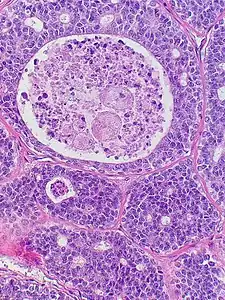

Micrograph of an adenoid cystic carcinoma of a salivary gland (right of image): Normal serous glands, typical of the parotid gland, are also seen (left of image), H&E stain. | |

- Histopathological image of adenoid cystic carcinoma of the salivary gland infiltrating a nerve (center), H&E stain